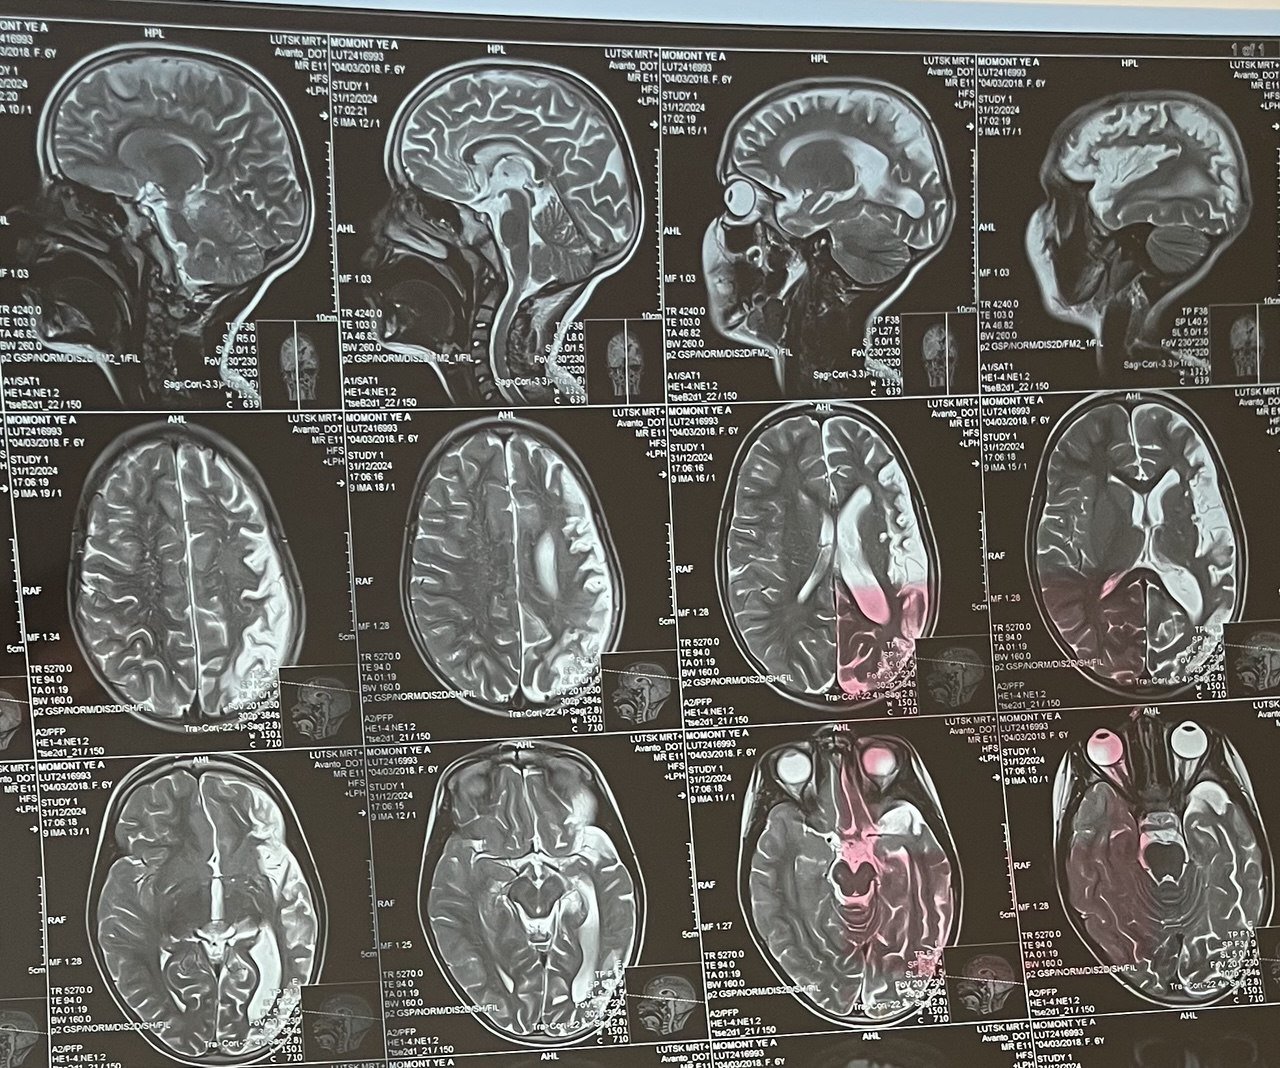

«При першому клінічному епізоді ми ставили діагноз аутоімунний енцефаліт, адже бачили характерні зміни на МРТ, а також зміни в об’єктивному стані Лізи. Через рік відзначилась негативна динаміка на МРТ головного мозку, зміни на електроенцефалографії (ЕЕГ), які характерні для енцефаліту Расмуссена. Саме тому лише через рік ми визначили точний діагноз Лізи. Специфічного лікування енцефаліту Расмуссена, на жаль, не існує, адже достеменно невідома точна причина виникнення цієї хвороби.